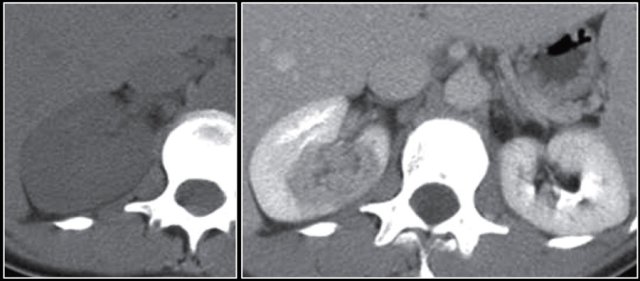

The image shows bilateral involvement of the kidney and a bone lesion in a patient with B-cell lymphoma.

Here another patient with lymphoma located in the mediastinum, pancreas (arrow) and in both kidneys.

Diffuse enlargement of both kidneys in a patient with lymphoma.

Continue with the PET-CT.

PET-CT shows diffuse renal involvement and also positive periaortic lymph nodes (arrows).